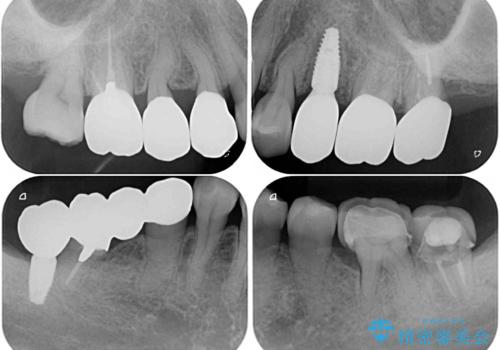

- 治療をおこなって以来、クラウン周りの歯肉から出血が続くとのことで来院された患者様です。

診察を行ったところ、クラウンと歯の境目が不適合で汚れが溜まりやすく、炎症を起こしている状態でした。

治療を終えたばかりですが、出血を改善するためには作り直しが必要と判断し、オールセラミッククラウンにて補綴治療することとしました。

他にも、咬合時に痛みを感じる歯や、欠損により咬みにくい奥歯などをインプラントを用いて治療を行うこととしました。